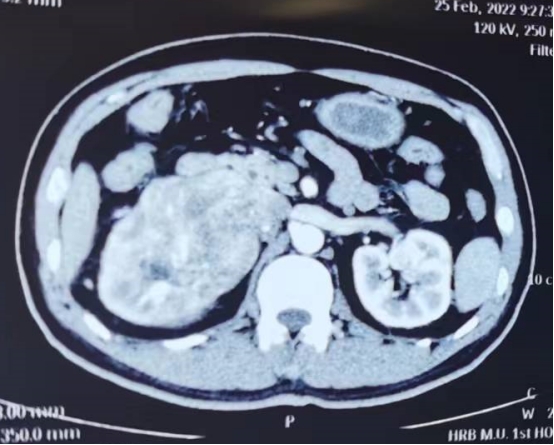

59岁的刘先生,因反复腰痛伴轻微血尿辗转多家医院未果,来到ac米兰官网中文网站一院泌外科三病房求治,确诊为右肾肿瘤,但检查均未提示有腔静脉癌栓,修有成、刘赞组织科内术前讨论,依据影像学检查考虑有肾门淋巴结肿大合并有腔静脉癌栓可能性大。

术中,因瘤体体积较大,恶性度高,最关键的是肾门部浸润严重并伴有淋巴结肿大。右肾动脉解剖不出来、找不到,为了手术安全,修有成、刘赞团队凭借丰富的手术经验,在没有受到浸润的地方,主动脉起始部腔静脉和主动脉之间找到右肾动脉予以阻断,腔静脉壁予以部分切除并用可吸收线缝合腔静脉,然后切除肾脏和肿大的淋巴结,手术艰辛、复杂、凶险,在团队的配合下,经五个小时的不懈努力,终于成功完成了手术,术中出血量少,未给予输血,患者安返病房。